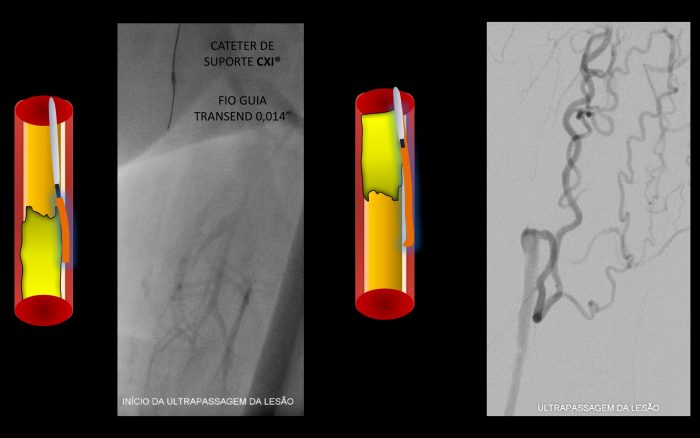

Paciente com história de claudicação dos membros inferiores para curtas distâncias, já submetido a angioplastia do membro inferior direito, retorna ao serviço com piora dos sintomas no lado esquerdo, sem lesão trófica (Rutherford 3)